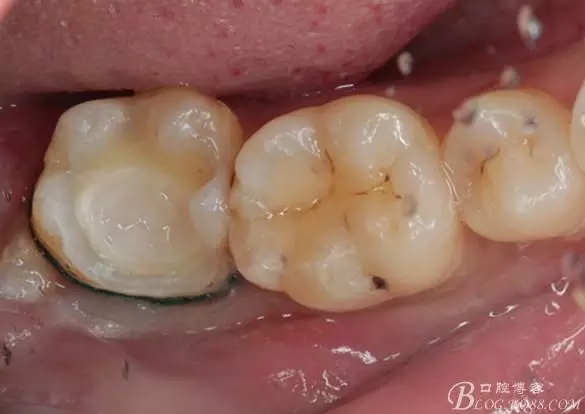

一周后復(fù)診,37臨時(shí)充填物完好。去除臨時(shí)充填物,清潔基牙,試戴嵌體,就位良好,邊緣密合。取下嵌體,常規(guī)處理,9.5%HF處理20S,沖洗一分鐘,95%酒精蕩洗5分鐘?;劳磕?7%的磷酸凝膠,釉質(zhì)區(qū)域酸蝕30S,本質(zhì)區(qū)域15S。粘固用的是3M第八代粘接劑套裝,照說明書逐步操作。最終固化時(shí)涂滿阻氧劑,每個(gè)牙面最少光照30S,光固化燈用漸強(qiáng)模式。常規(guī)調(diào)合,配合硅膠尖套裝拋光。術(shù)后常規(guī)醫(yī)囑,不適隨診。